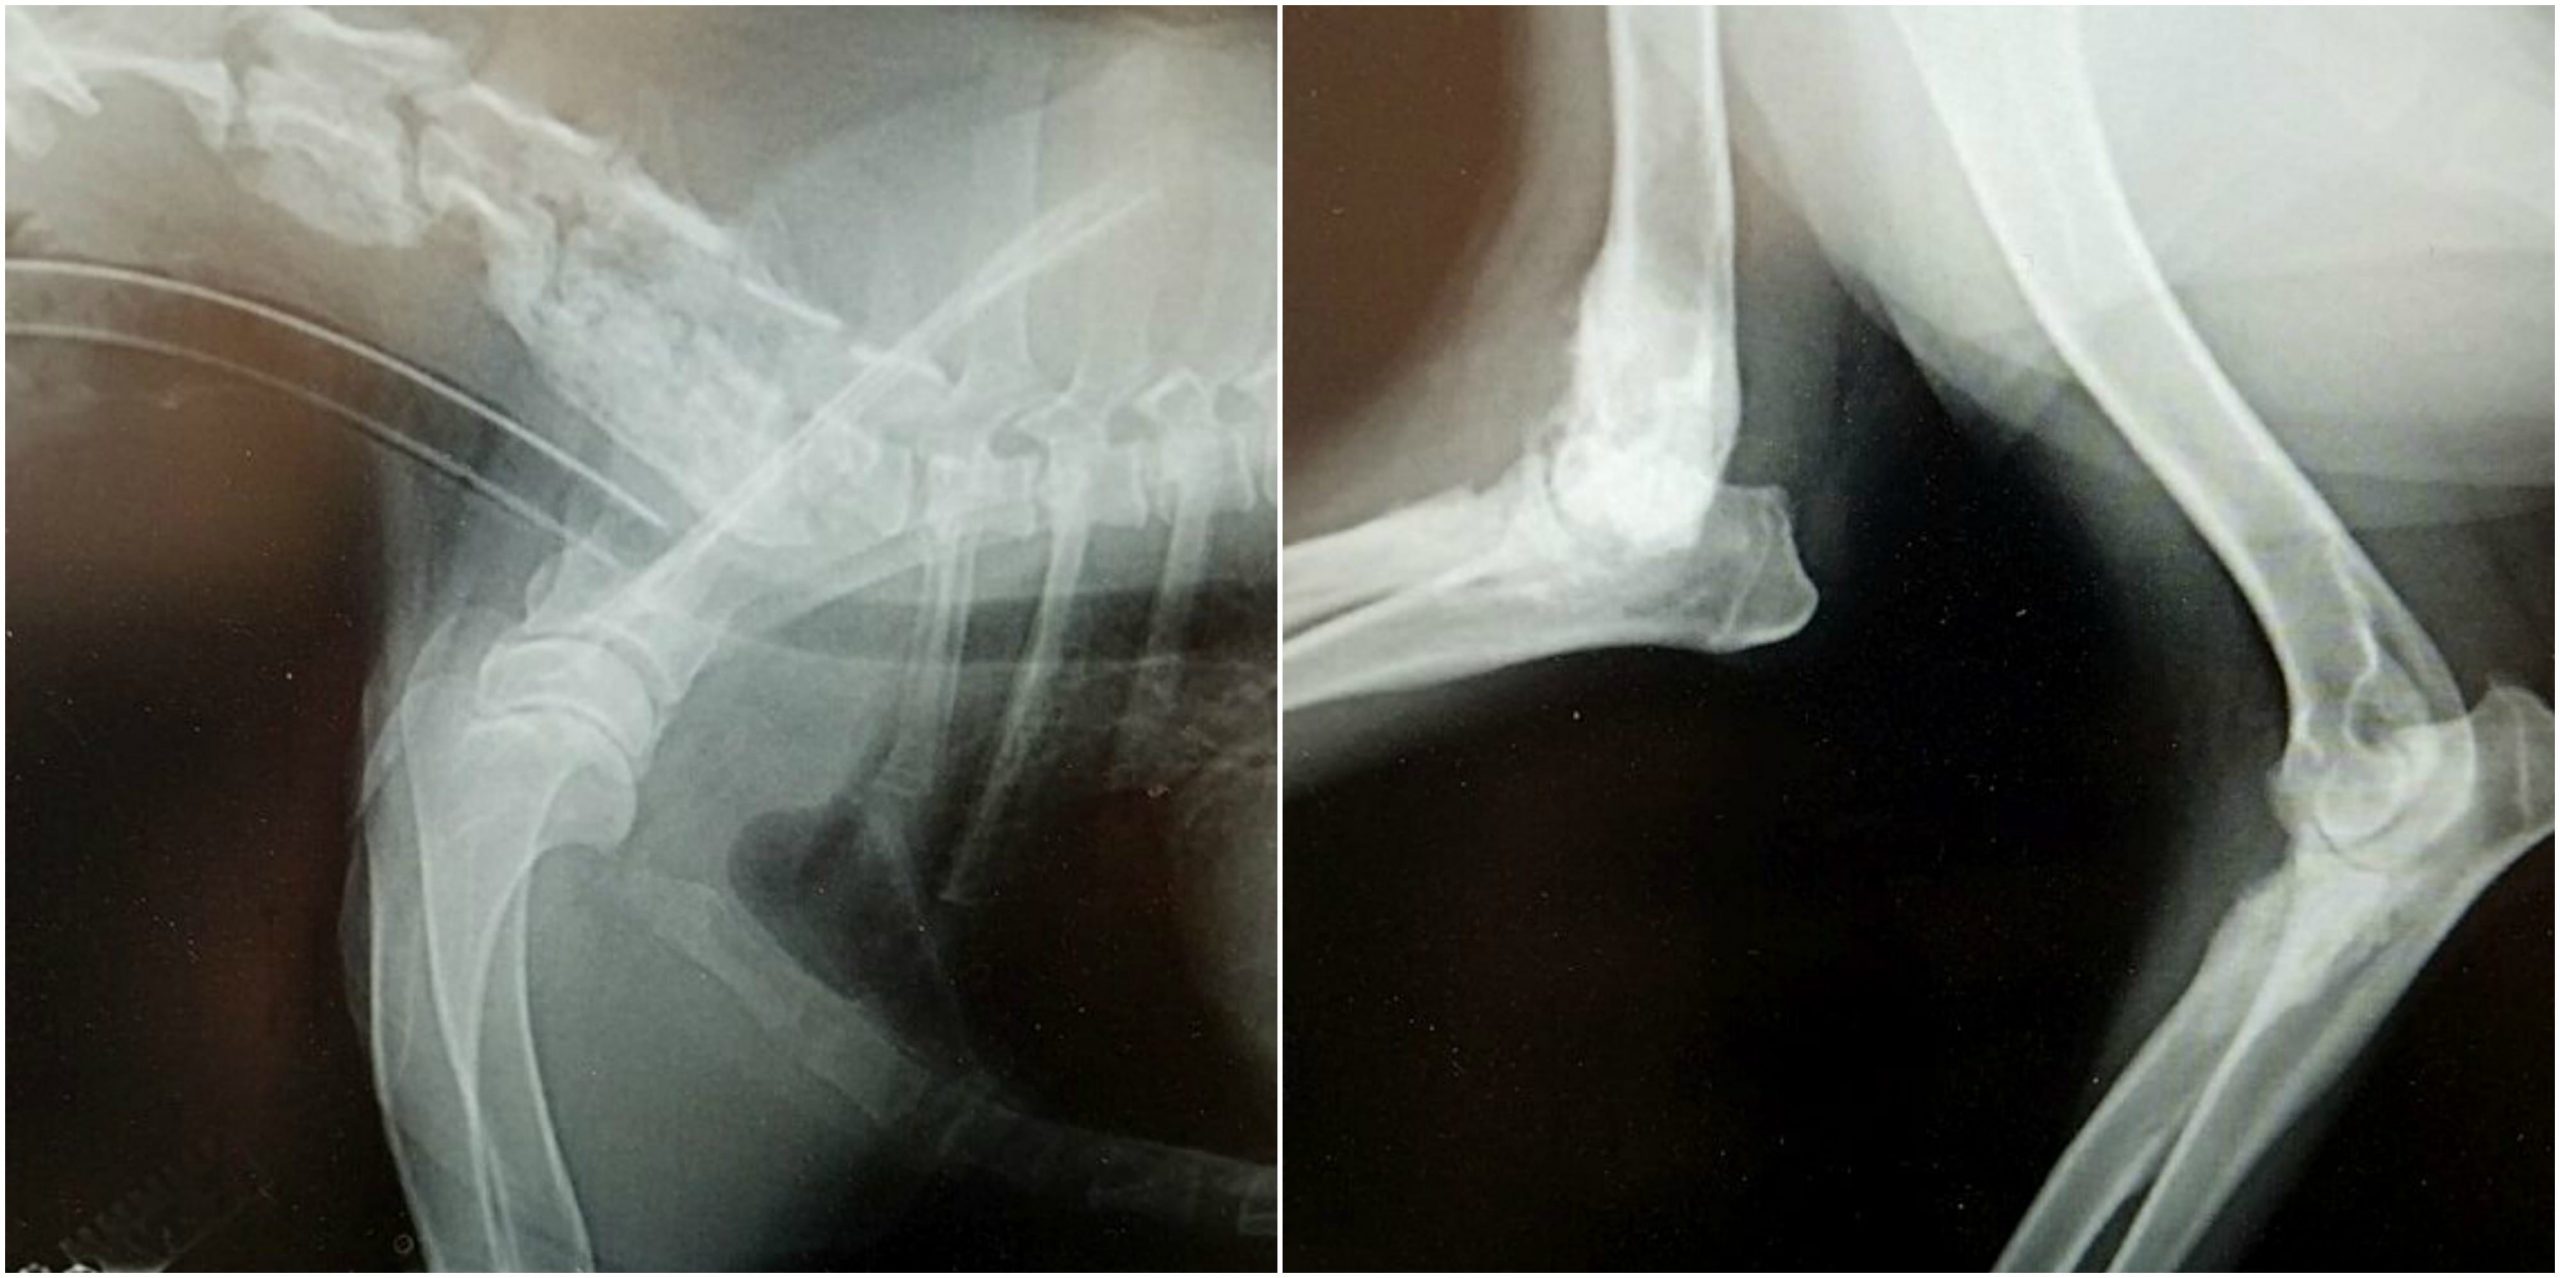

- Lameness or swelling in bones/joints

- X-rays of the chest/limbs

- Repeat x-rays may be necessary if there were significant lung or bone changes caused by the disease